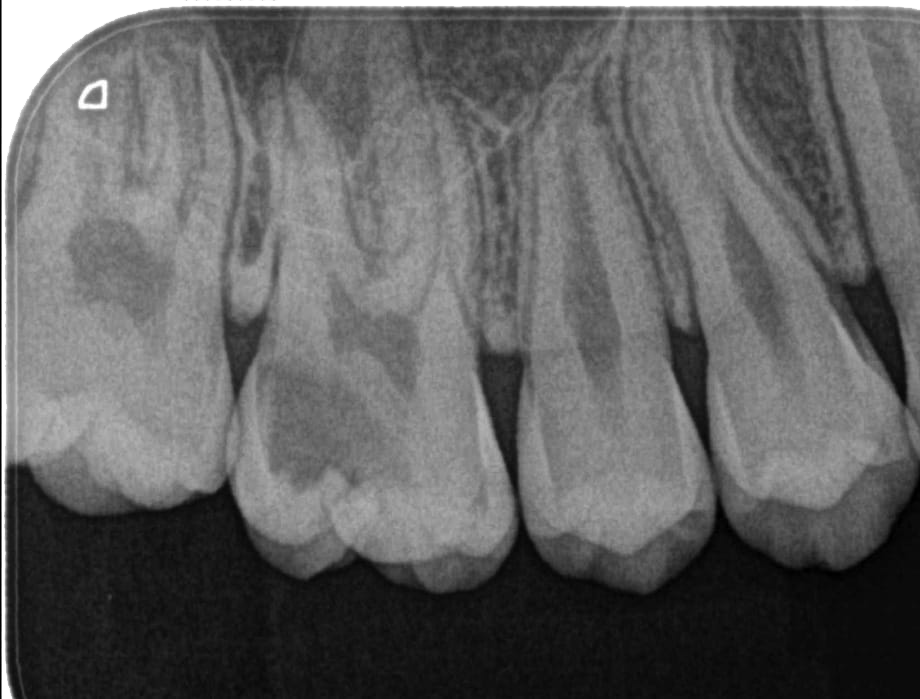

A maioria das infecções nos dentes é crônica e silenciosa. Não dói, não incha, não aparece. O dente pode estar infeccionado há anos — e você não sabe. Só a radiografia detecta.

Raio-x real: lesão escura no ápice da raiz indica infecção ativa — sem dor.

Outro sinal que passa despercebido: o dente que escurece aos poucos. Muita gente acha que é "da idade" ou "do café". Na verdade, pode ser um dente morto com infecção ativa por dentro.